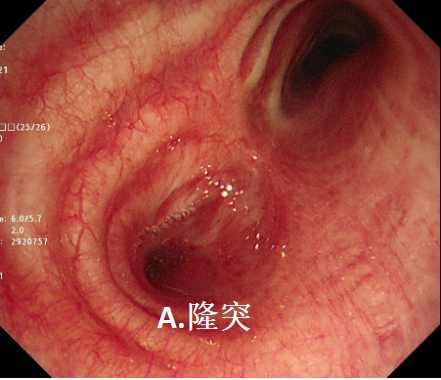

镜到之处,目之所及:左主支气管开口呈瘢痕样狭窄,远端支气管闭塞。难怪CT上只看到一边的肺,现在真相大白了!患者目前左肺开口处被肺瘢痕完全封堵,形同虚设,只有右肺可以用。

图2 支气管镜下表现